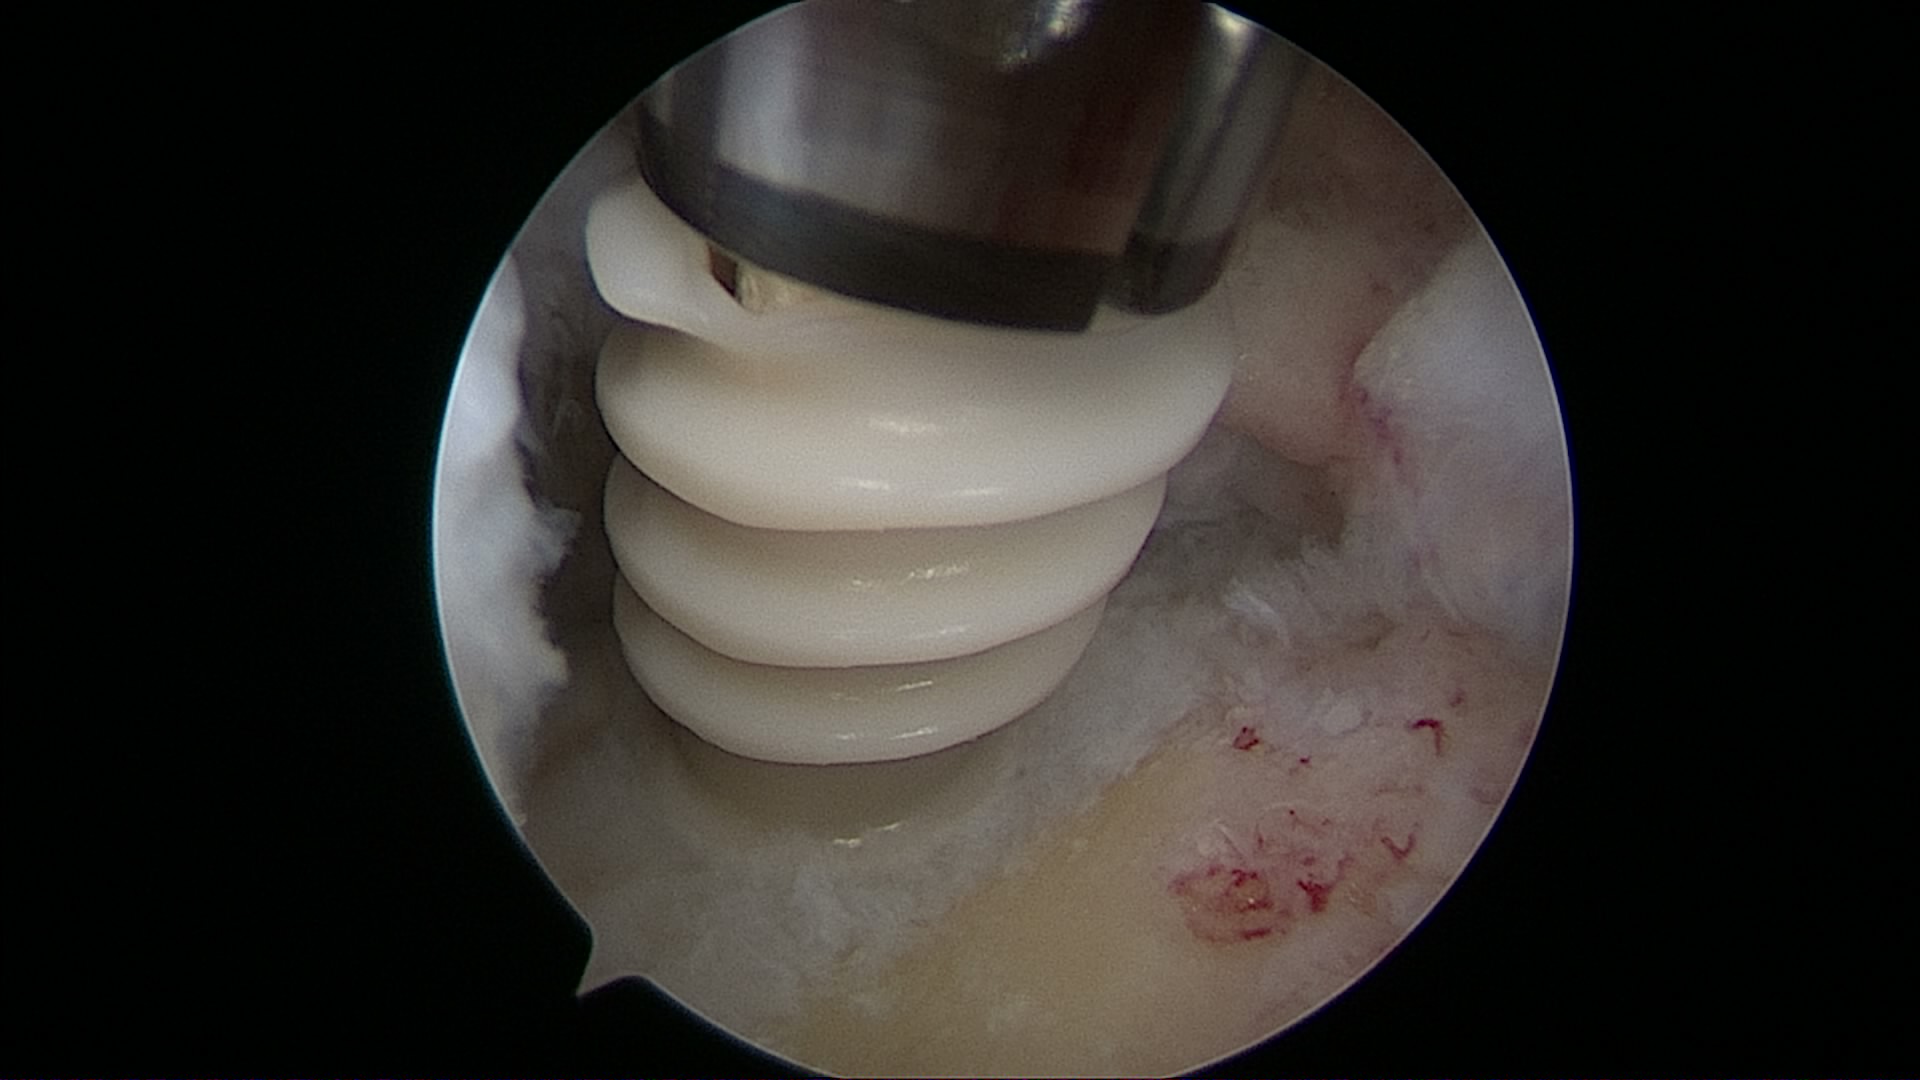

Lesión de Manguito Rotador

Reparación de Manguito Rotador con suturas y anclaje

Cirugía de reparación de manguito rotador con suturas y anclajes

Cirugía manguito rotador con suturas y anclajes